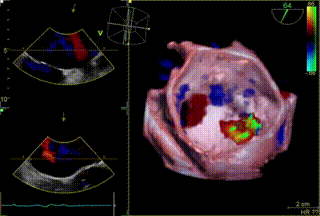

经食道超声显示(术前):二尖瓣前叶长度35mm,后叶长度11.7mm,对合高度约4.8mm,对合深度约为9.7mm,VC 7.2mm, MVA 5.9cm²。

术前TEE显示二尖瓣重度反流,反流位置位于A2/P2区

患者全麻后,在经食道超声心动图和X射线引导下,经股静脉入路,将申淇淇麟®系统瓣膜夹顺利送至二尖瓣A2/P2区域,经调整位置使瓣膜夹垂直对合缘,跨瓣。由于后瓣长度较短,很难同时捕获,遂应用单瓣叶独立捕获功能,成功地分别捕捉二尖瓣前叶和后叶,经超声心动图反复确认瓣叶夹持牢固,反流量减少,跨瓣压差4.3mmHg。遂释放瓣膜夹,超声心动图评估瓣膜夹位置和功能良好,瓣膜夹活动度低,手术顺利完成。